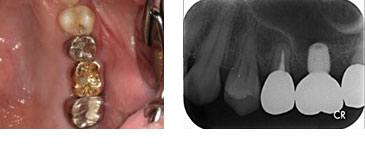

右上5番歯根破折 抜歯即時インプラント埋入

BEFORE

AFTER

| 金額 | ¥460,000(税抜) |

| 期間 | 約3ヶ月 |

| リスク | オペから6週までは過大な力がかかると骨の2次安定が得られないことがあるため、注意を要する。 |